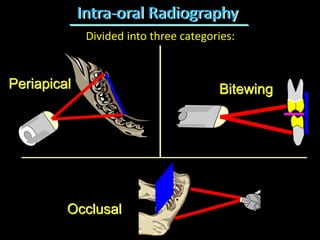

1. The document discusses various intra-oral radiographic techniques including the paralleling cone technique and bisecting angle technique.